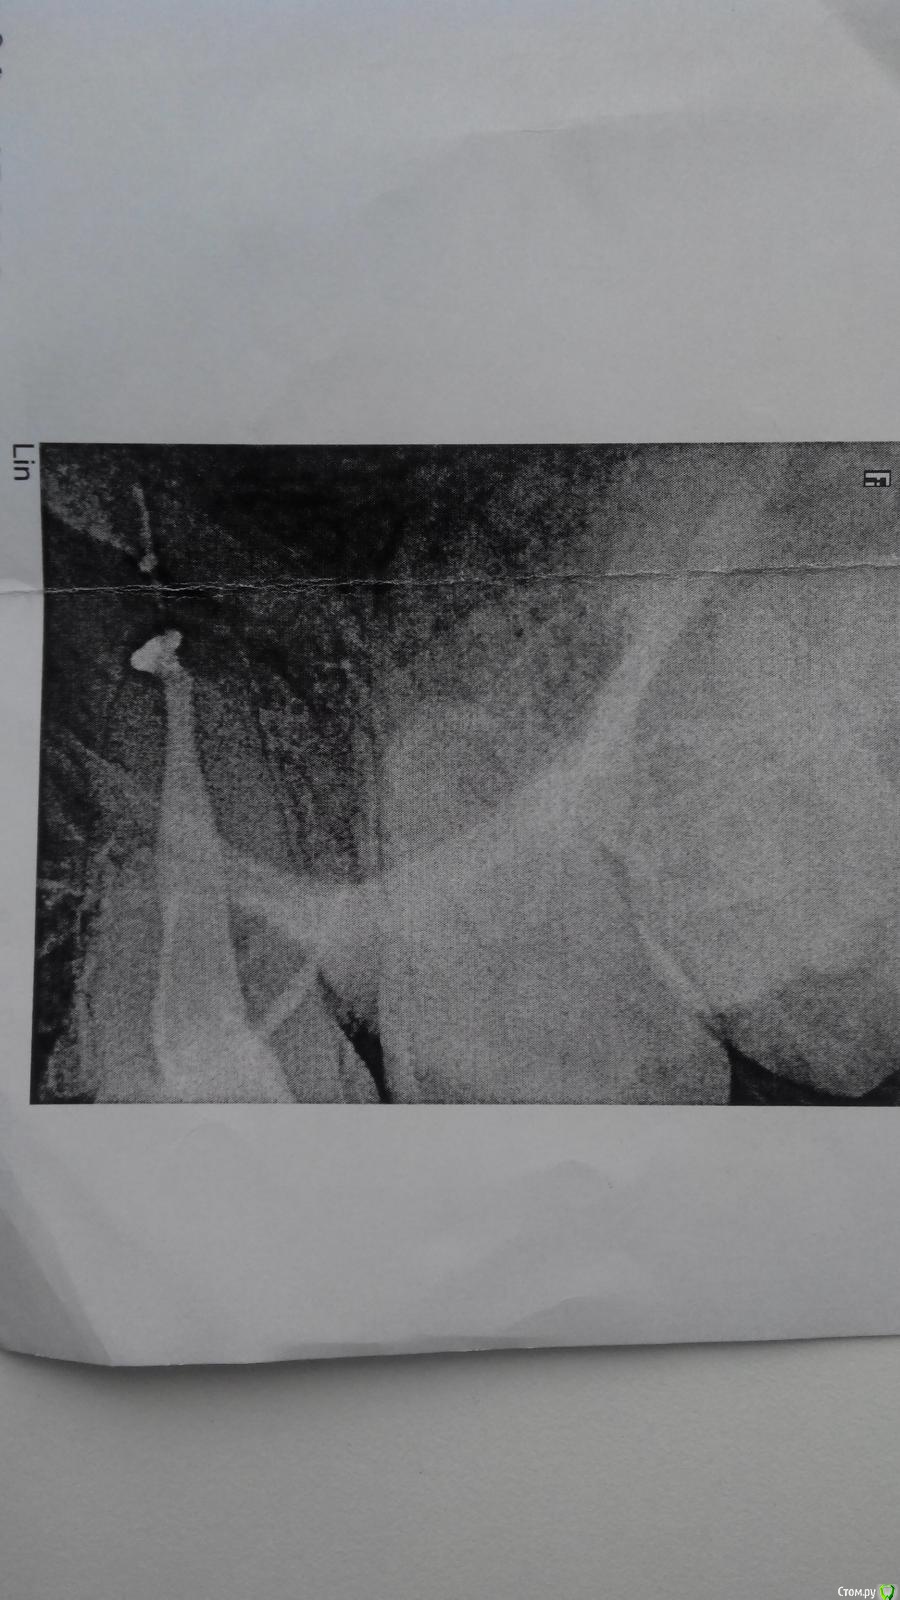

-Ruslan- Опубликовано 25 марта, 2019 Поделиться Опубликовано 25 марта, 2019 (изменено) Здравствуйте! В 2016 году врач неудачно пролечил мне 26 зуб. Буквально через неделю начался острый синусит. Из носа текла 24 часа в сутки прозрачная липкая жидкость. Потом я стал применять сосудосуживающие капли и стало полегче. Потом был наверное мой первый гайморит в жизни. Я промывал самостоятельно нос и вроде как гной ушел. Но где-то через год началась астма(никогда не болел ей раньше, среди родственников астматиков нет). Я начал задыхаться по ночам. Появилась одышка. Из легких стала отходить желтоватая желеобразная мокрота. В этом году после просмотра КТ снимков на компьютере челюстной хирург поставил мне одонтогенный гайморит от 26 зуба. На мой вопрос что мне делать дальше, сказал нужно делать операцию, но отговорил в связи с сильными осложнениями. Сказал что многие живут с подобной проблемой. Сейчас меня беспокоит затрудненное дыхание ночью, астматические проявления, и обильные выделения из носа примерно до обеда, которые убираются с помощью сосудосуживающих каплей. Причем достаточно одной капли в левую ноздрю и в принципе можно жить. Правда ночью нос совсем плохо дышит и приходится дышать через рот. Скажите это возможно вылечить или смириться и жить дальше? https://yadi.sk/d/I_QaWJS5cDsCFg КТ снимок (302 мб) Изменено 25 марта, 2019 пользователем -Ruslan- Ссылка на комментарий